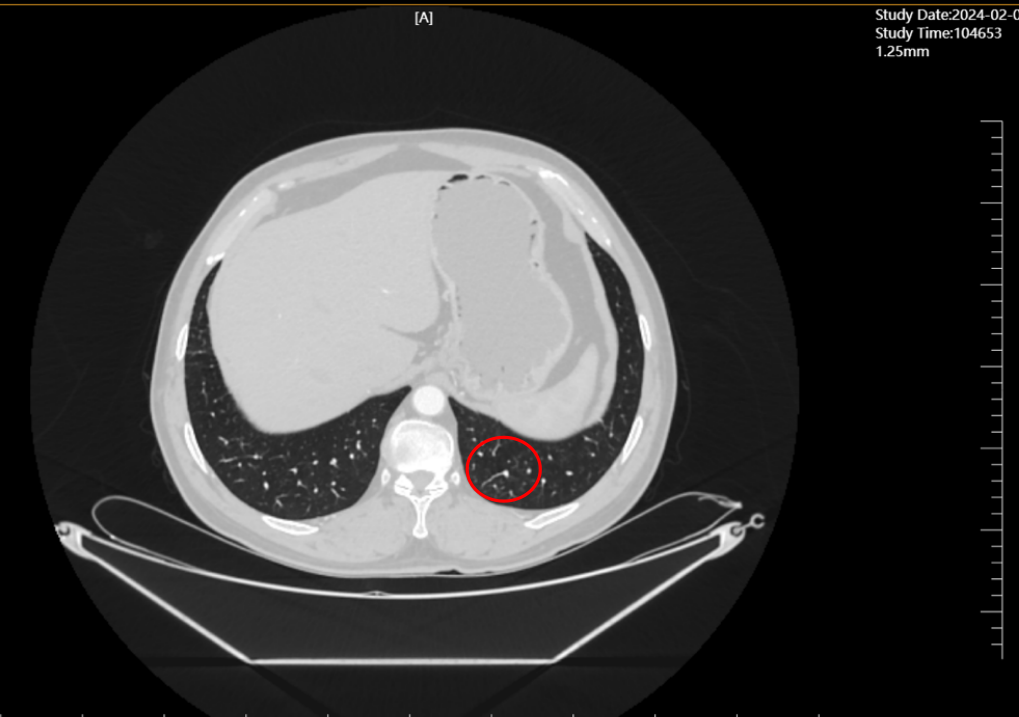

2024年2月(单药维持3个月),经影像科与肿瘤科联合评估,达到完全缓解(CR)——这是晚期肺癌治疗中的“技术里程碑”,意味着体内可检测肿瘤病灶完全消失。

2023年11月(联合治疗5周期),CT显示肺部原病灶大部分退缩为磨玻璃影,技术层面验证“肿瘤活性显著降低”;